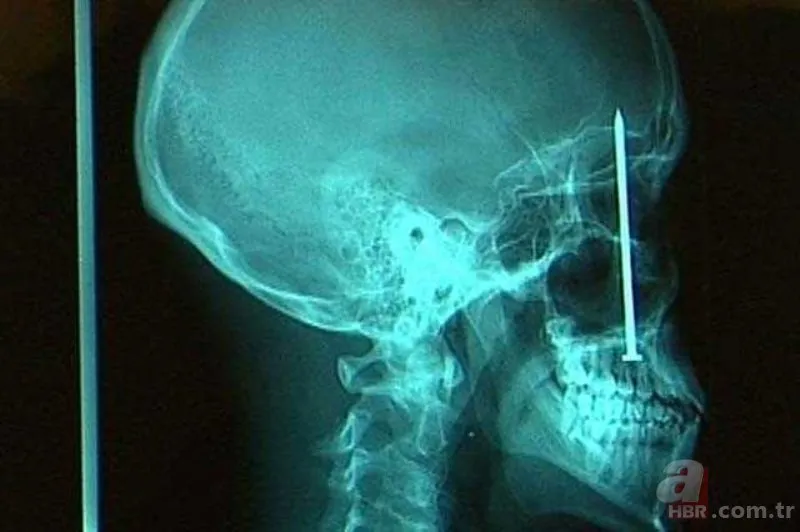

Bir inşaat işçisi bir gün doktora gitti. Dişi ağrıyan ve bulanık gördüğünü söyleyen adamın sorunu ise 20 yaş dişi değildi. Kafatasında bir çivi bulunan adam, bir hafta önce çivi makinesi ile çalışırken bir sorun yaşamıştı. makine tepmiş, adamın ağzından içeri bir çivi göndermiş ve bu çivi kafatasına kadar gitmişti!